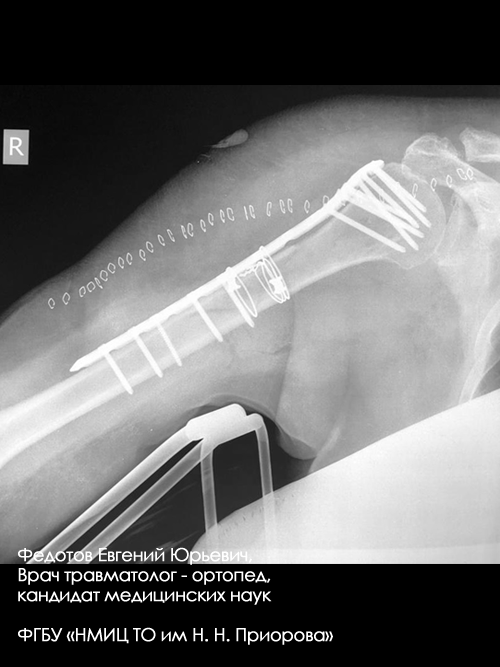

Пациент с оскольчатым переломом среднего отдела плечевой кости.

Выполнена операция: металлоостеосинтез плечевой кости стержнем с блокирующими винтами, введенным ретроградно.

Гипсовая повязка после операции не применялась, сразу после операции начата физкультура для суставов и мышц конечности.

Результат через 4 мес. после операции.

Видно, что мышцы, функция суставов полностью восстановились.

Пациентка с переломом среднего отдела плечевой кости.

Результат через 2 мес. после операции.

Функция конечности полностью восстановились.

Закрытый перелом ср/3-н/3 плечевой кости со смещением.

Операция: открытая репозиция отломков ср/3-н/3 плечевой кости, остеосинтез пластиной и винтами